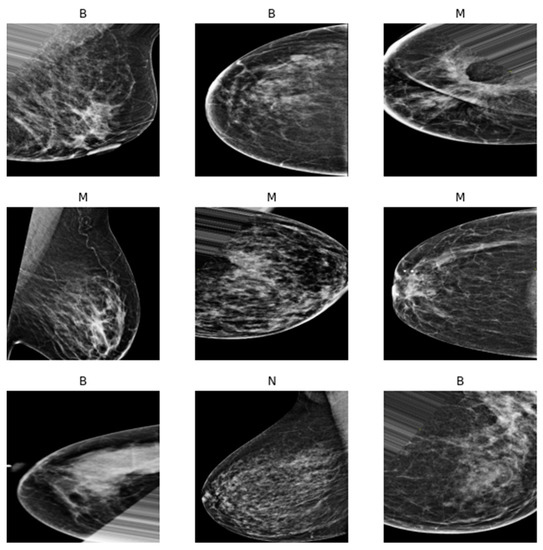

3.1. Dataset Descriptions

3.4.1. First Experiment

3.4.2. Second Experiment

3.4.3. Third Experiment

3.4.4. Fourth Experiment

| Experiment | Benign | Malignant | Normal |

|---|---|---|---|

| Experiment 1 | 192 | 268 | 0 |

| Experiment 2 | 40 | 236 | 360 |

| Experiment 3 | 360 | 236 | 1044 |

| Experiment 3 Balance Dataset | 236 | 236 | 236 |